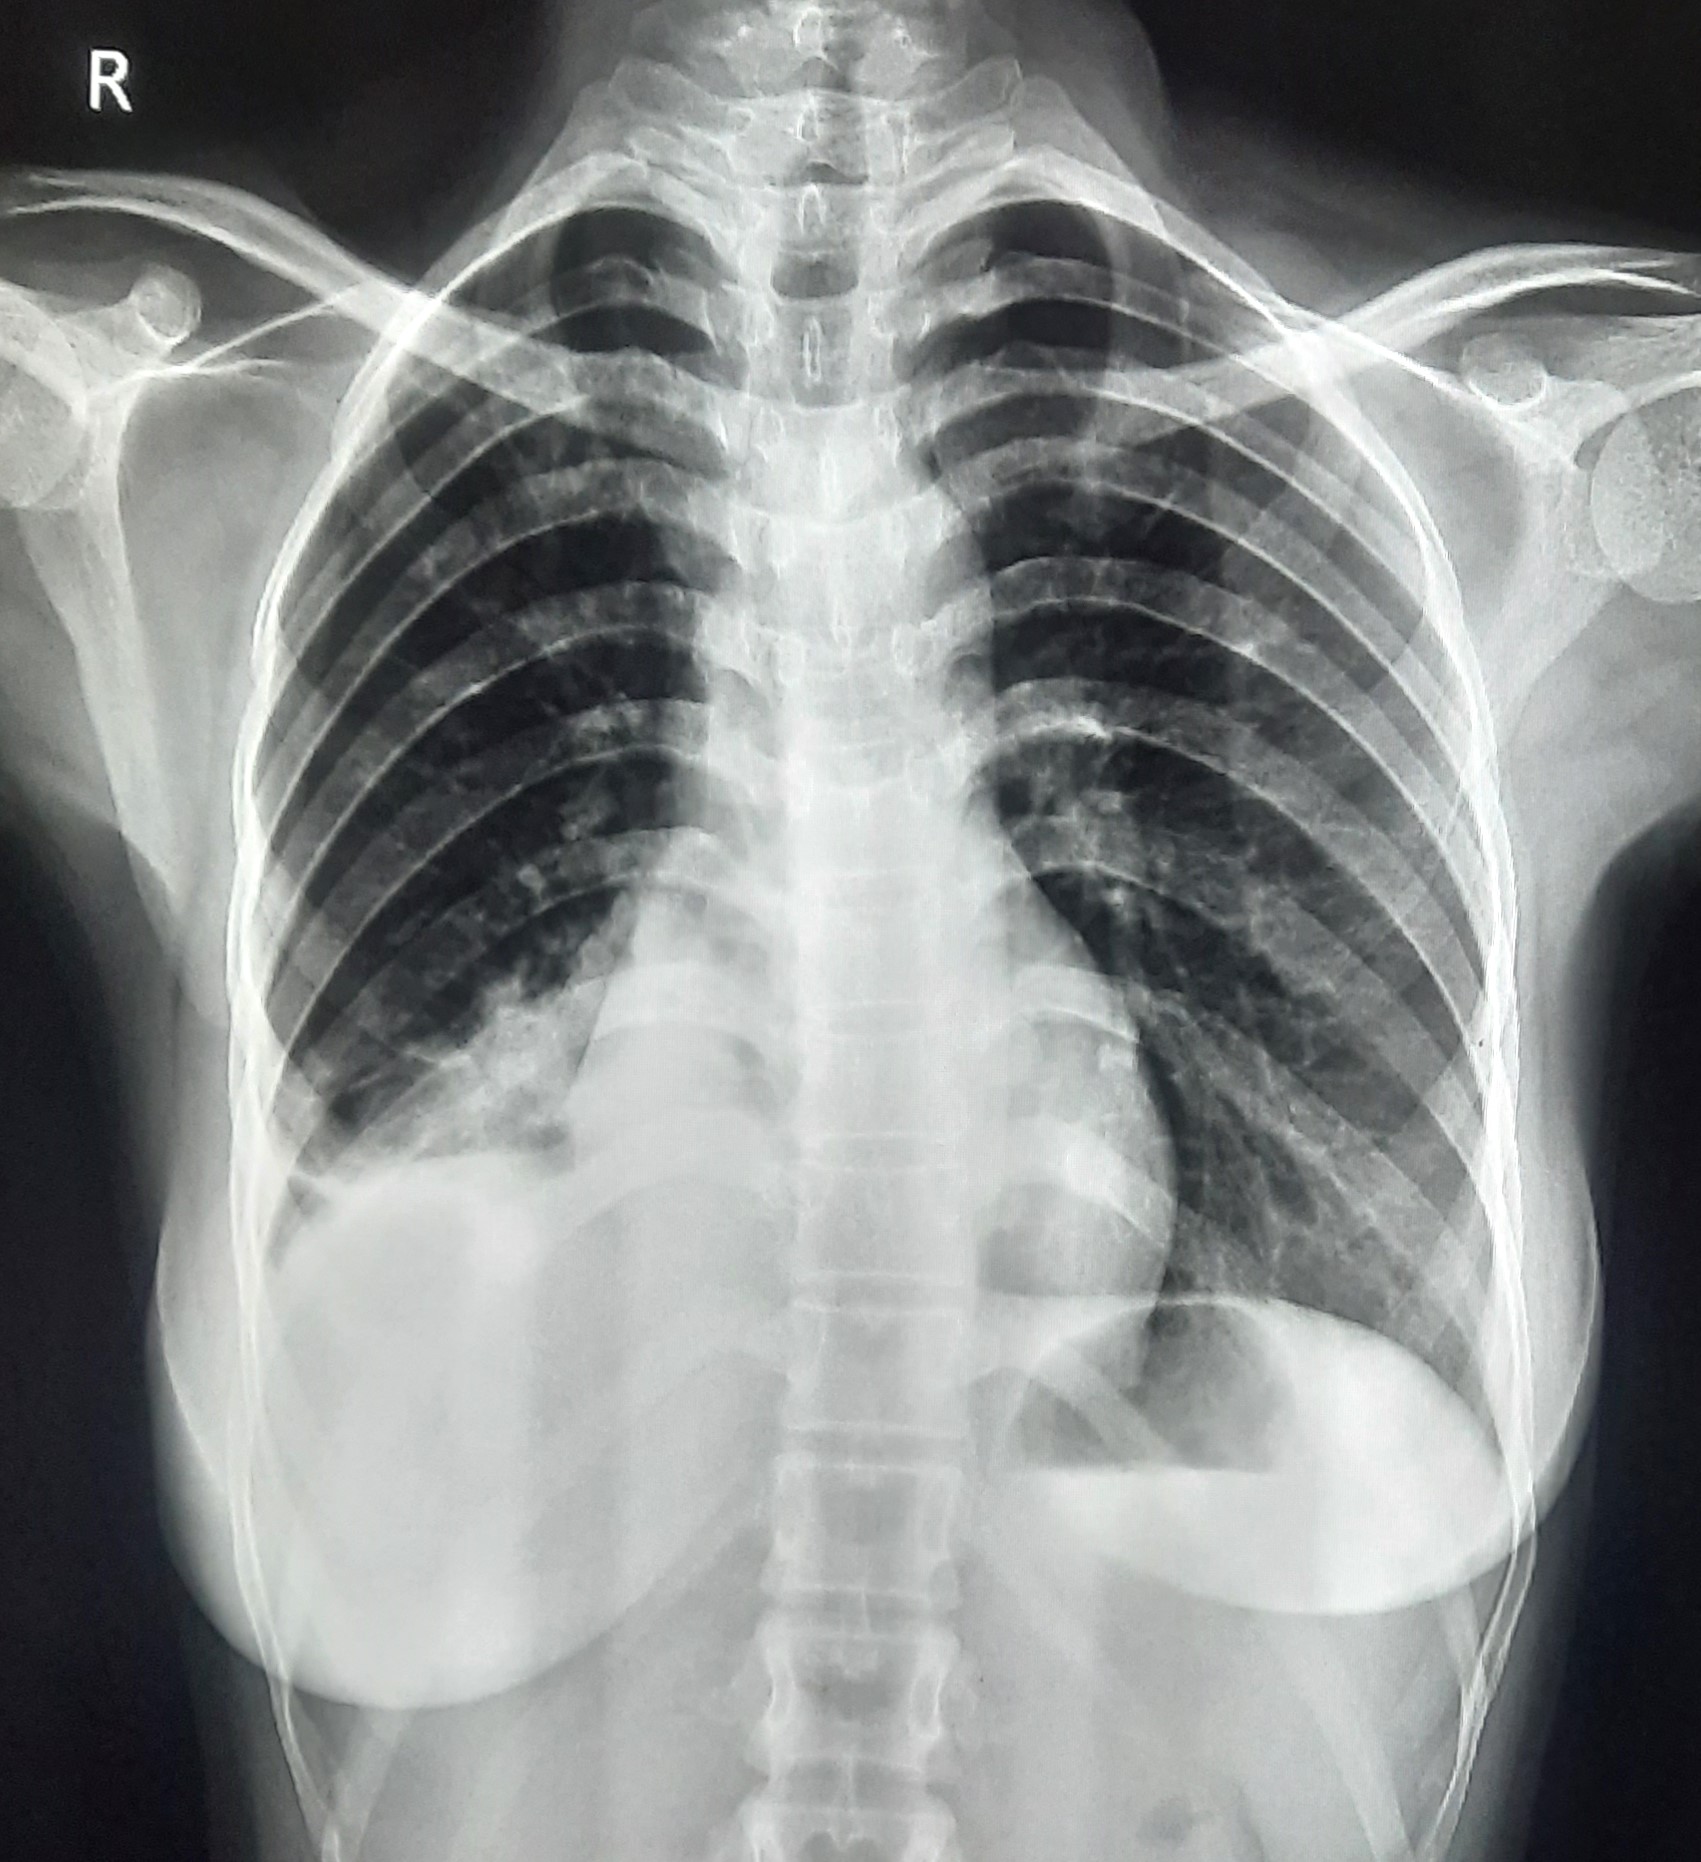

| 60 | IGGMC, Nagpur, Nagpur | P2 | 29-4412 | Ritesh Uikey | Consent taken on Paper | 30 Yrs. |

Provisional Diag : Pulmonary Tuberculosis

Final Diag : Pulmonary Tuberculosis |

TB Case (Confirmed) | Bilateral Lung Infiltration Present & Right Upper Zone Cavity Present | Abnormality visible on x-ray |